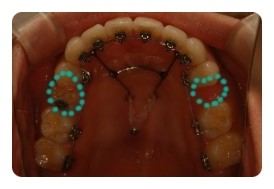

( 상악비교 )

▲ 발치 전 - 왼쪽유치 1차삭제, 오른쪽영구치 발치 예정

▲ 6월 - 스크류식립 후 본격적으로 상악당기기 1개월차

조신하지못한 저의 잦은 어금니 브라켓탈락 ㅠㅠ 에도 불구하고 잘 이동하고 잇는듯해요